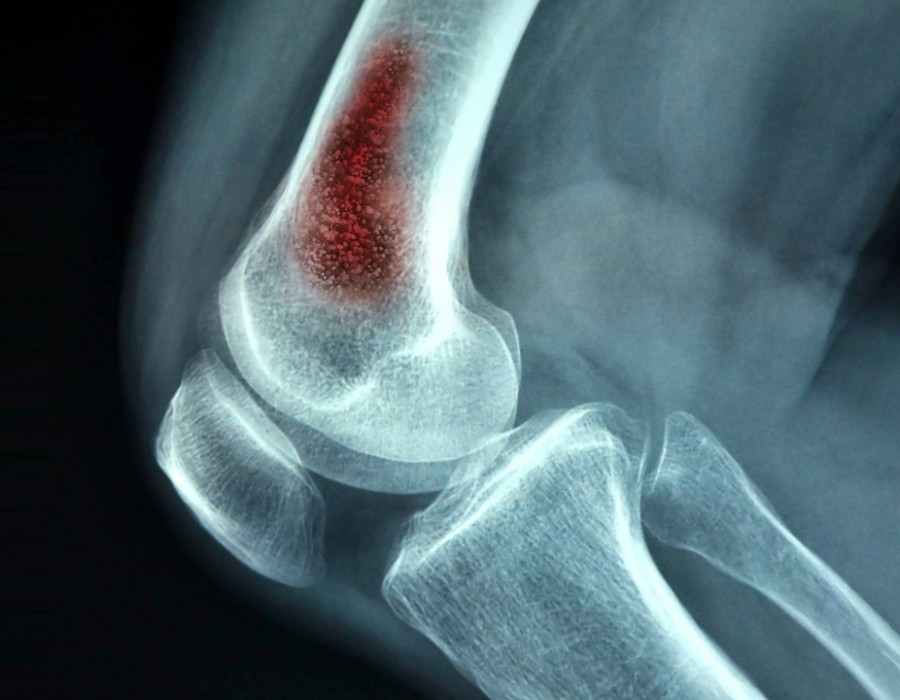

Bone infections, also known as osteomyelitis, can be caused by various factors. Here are some common causes:

Hematogenous Spread: When bacteria from another part of the body travel through the bloodstream to the bone.

Contiguous Spread: When an infection from nearby tissues, such as skin or joint infections, spreads to the bone.

4. Trauma or Injury: Severe injuries or trauma, such as compound fractures where the bone is exposed, can lead to infections.Top orthopedic doctor in kota The break in the skin and underlying tissues provides a pathway for bacteria.

8. Existing Infections: Infections like those of the skin (cellulitis) or joints (septic arthritis) can sometimes spread to the bone.